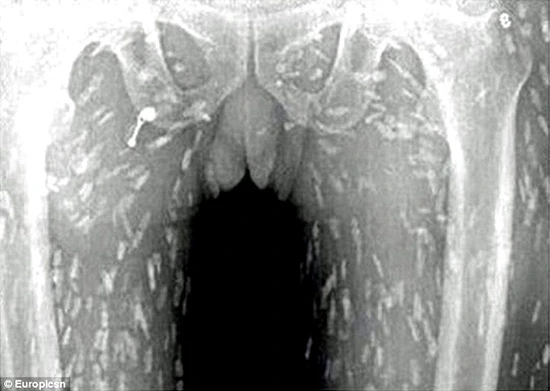

Hình X-quang của một người TQ khiến bác sĩ khiếp đảm khi thấy sán chi chít khắp cơ thể. Sushi là nguồn gốc tình trạng giun sán ký sinh này.

Một người đàn ông Trung Quốc nghiện sushi tìm đến bác sĩ trong tình trạng đau bụng và ngứa da. Ông bị sốc khi biết giun sán ký sinh là nguyên nhân của tình trạng này. Ảnh chụp X-quang cho thấy sán có ở toàn thân bệnh nhân.

Daily Mail ngày 5-6 đưa tin người đàn ông Trung Quốc tìm đến Bệnh viện Nhân dân Số 8 ở Tỉnh Quảng Đông, Trung Quốc phàn nàn về chứng đau dạ dày và ngứa da trong thời gian dài. Sau khi quét toàn bộ cơ thể, các bác sĩ đã nhận được hình ảnh khá kinh dị: Cơ thể bệnh nhân dày đặc giun sán.

Tiến sĩ Yin từ Bệnh viện Nhân dân số 8 Quảng Châu nói rằng ăn thức ăn chưa nấu chín nhiễm trứng sán dây sẽ gây ra bệnh giun sán. Khi trưởng thành, sán có thể đi vào máu người, nếu lên não có thể gây tử vong. Nhìn hình X-quang, có lẽ nhiều người không bao giờ dám ăn cá sống.